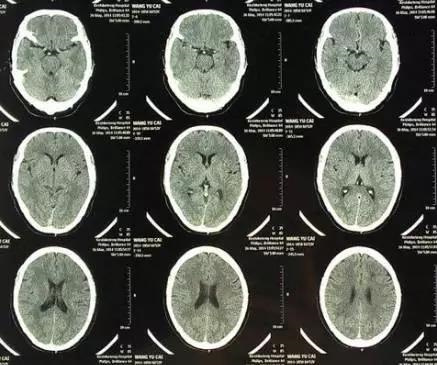

CT意为X线计算机断层摄影,是用X线束对人体某部进行断层扫描,获得人体被检部的断面或立体图像。CT可以提供人体被检查部位的完整三维信息,可使器官和结构清楚显影,清楚地显示病变。就像把一片面包切成片来看。优点是可以分层看,经计算后可以显示出更多的组织信息。